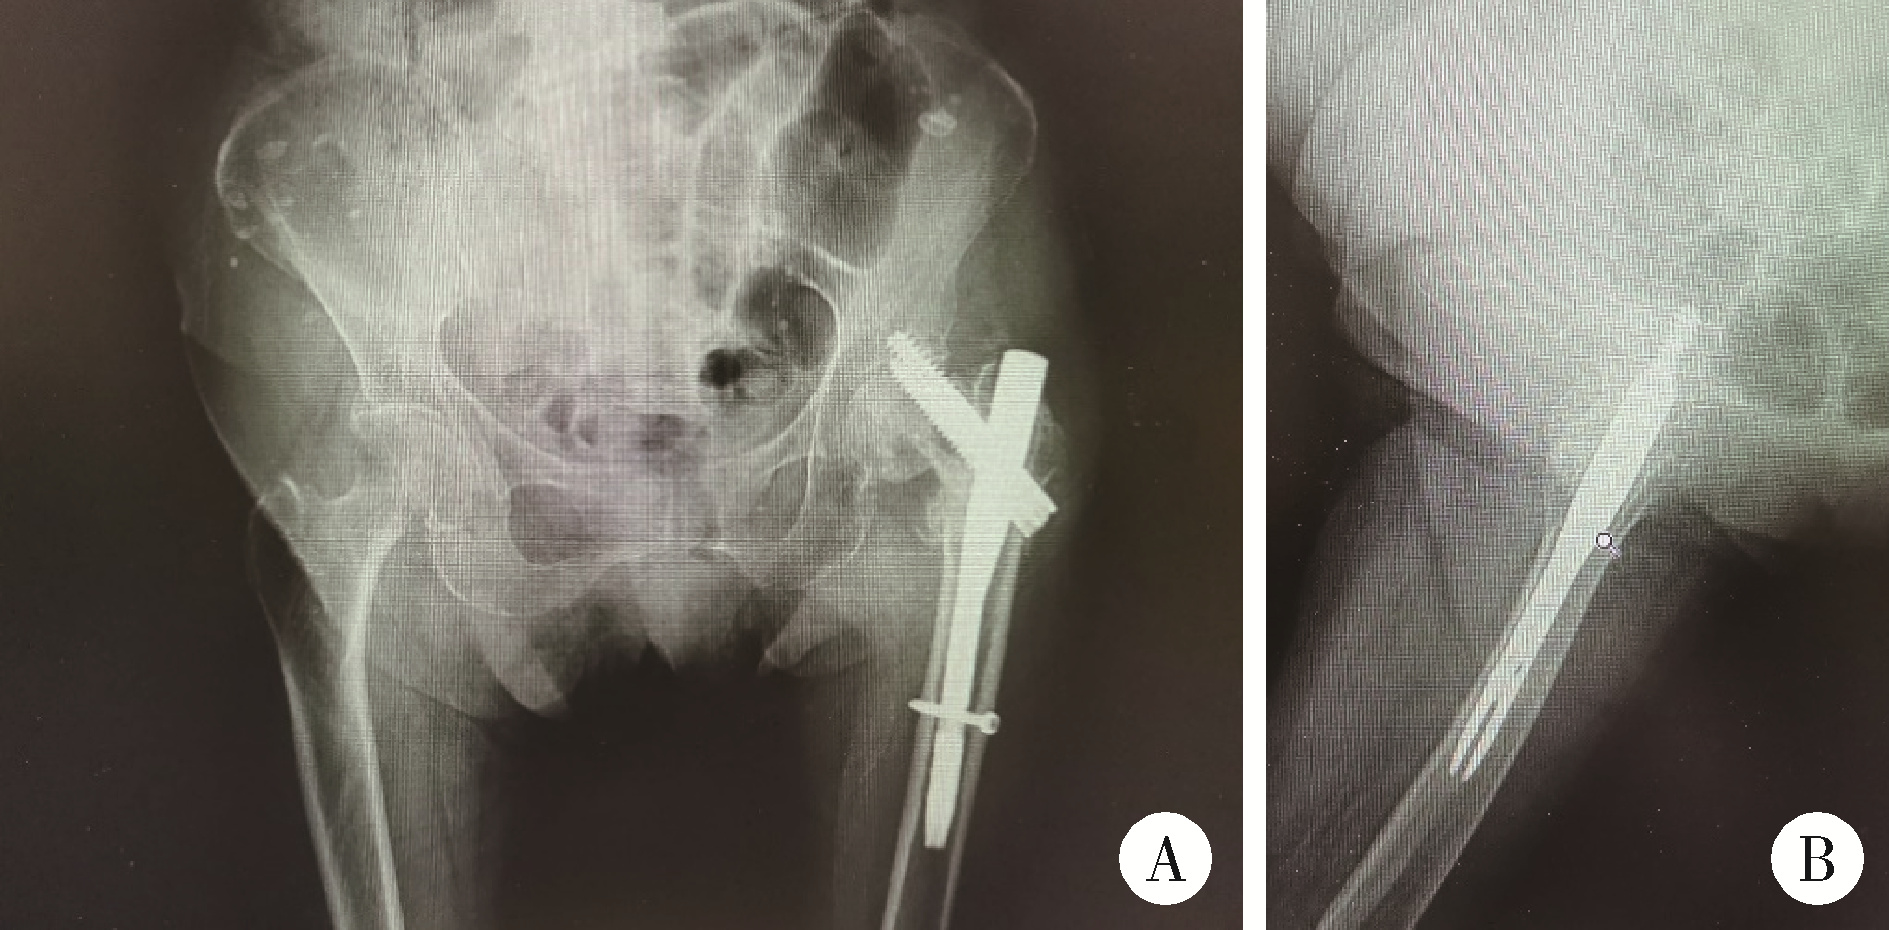

Figure 6

X-ray films of patient after left hemiarthroplasty A, X-ray films of both hips; B, left hip lateral view, post-left hip hemiarthroplasty."